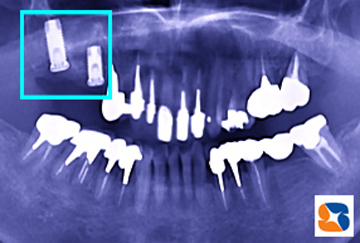

インプラント成功の秘訣には、インプラント体を支える強固な骨のサポートが、絶対に欠かせません。歯周病が原因で抜歯となるケースでは、骨は大きく失われています。そのためこの患者様の場合、抜歯後すぐに凹状の骨を埋める施術(インプラント手術を前提に抜歯をされる方には、無料です。)も同時におこないました=上の写真。

10ヶ月後、抜歯した跡のインプラント植立予定部分=写真=には、強固で厚みのある骨の存在が認められました。しっかりした骨の中にインプラントを入れると、治療は成功します。

2本のインプラントが上手く植立=写真=されました。5ヶ月後には、インプラント体の上に、白いセラミックの歯を装着して完成予定です。